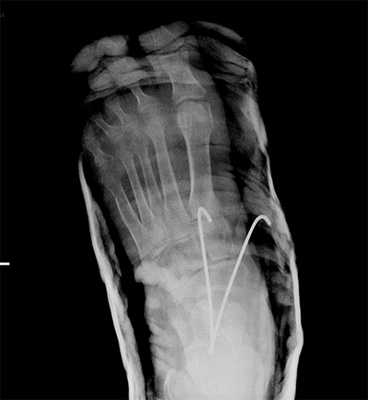

У больного с повреждением шейки таранной кости делают закрытое вправление, при переломе шейки с ротационной деформацией и дорзальным смещением фрагмента более 5 мм показана операция - открытая репозиция и фиксация отломков, при переломе шейки с разрывом таранно-пяточной связки делают операцию с фиксацией фрагментов спицами или винтом, при нестабильном вывихе в подтаранном суставе делают либо закрытое вправление с фиксацией спицами, либо открытое вправление с применением фиксирующих устройств. Артродез делают по следующим показаниям: нарушение размеров и формы кости, нарушение соотношения между опорными колоннами, нарушение конгруентности таранно-ладьевидного и пяточно-кубовидного суставов, значительное расхождение суставных концов, которое препятствует сращению связок, хронический подвывих в поперечном суставе предплюсны. В далеко зашедших случаях хронической нестабильности артродез позволяет уменьшить боль в стопе и улучшить ходьбу. При разрушении таранно-ладьевидного сустава артродез приводит к диспропорции медиальной и латеральной опорных колонн, что может потребовать дополнительного вмешательства на пяточно-кубовидном суставе для восстановления симметрии. После артродеза срок иммобилизации в гипсовом сапожке составляет не менее 10 недель.

Рис. 10. Чрезкожная фиксация костей предплюсны после вправления вывиха в суставе Шопара, стопа в гипсовой лонгете